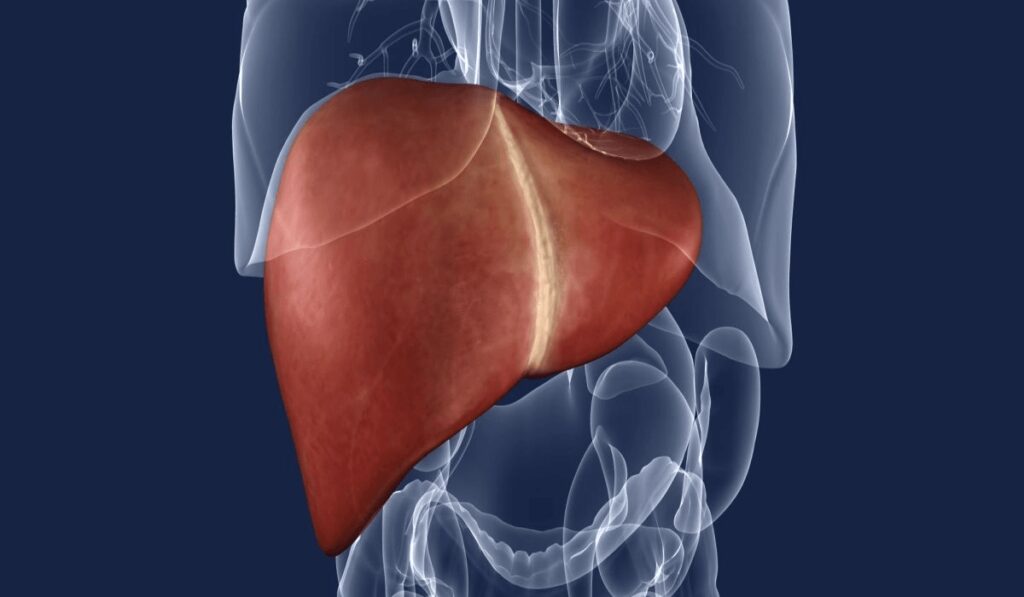

Ficatul gras sau steatoza hepatică reprezintă acumularea de grăsime în exces. Potrivit statisticilor, această boală afectează afectează 30 la sută din populație. Este o boală tăcută, pe care mulți pacienți nu știu că o au.

Boala „ficatului gras” afectează unul din cinci români FOTO: Arhivă, Adevărul